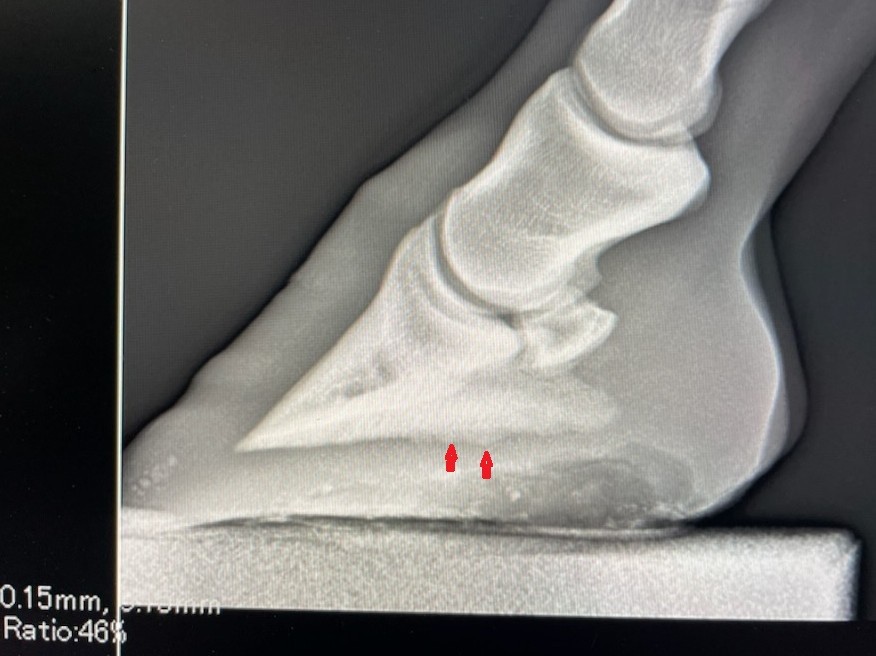

本馬は、自己所有として早期の競走馬デビューを目指し、昨年9月より育成牧場にて調教を進めていたものの、3月に左前肢に原因不明の跛行が見られました。経過を観察しつつ獣医による診察・検査を受けたものの原因が特定されない日々が続きました。今月に入り、再度、レントゲン検査を受けると「左前蹄骨炎」との診断でした。左前の蹄骨の側面に骨瘤のような影があり、跛行の原因との所見を踏まえて検討した結果、早期デビューへの目処が立たないため、このタイミングで所有馬整理の出品とさせて頂きます。母のレイトブルーミングはサラブレッドオークションで落札後、高知で5勝。優秀なファミリーに期待を寄せての産駒だけに残念でなりません。皆様には現状をご理解いただき、ご納得をいただいた上でのご検討、ご入札をお願いし、現状渡しのノークレーム、ノーリターンでお願いいたします。

調教を順調に進めていた段階では坂路で15-15まで乗れていたのですが、原因不明の跛行を見せてからは一進一退が続いている現状です。担当獣医の話では症例が少ないもので競走馬としては五分五分との見解です。装蹄を替えても体重の負重に耐えられなければ装蹄の意味がないですし、経過を見ながら対応していくことだと思います。(加藤ステーブル・加藤天明氏)